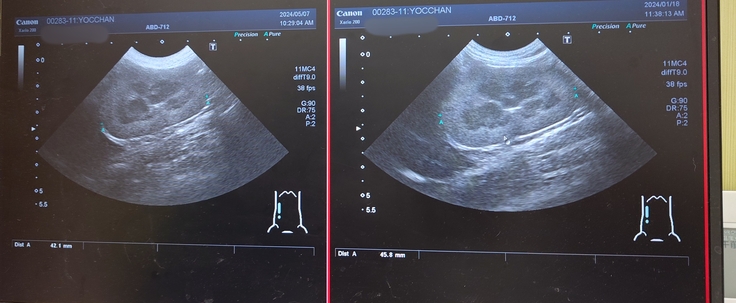

正常な右の腎臓腎盂。

画像の右側が前回のエコーで、左側が今回のエコー。

腎盂が肥大している左の腎臓。

腎臓のサイズは右側の腎臓が45.8mmから42.1mm、左側の腎臓が39.4mmから35.7mmになっていて、前回よりも腎臓の大きさが縮小していて、もしかしたら腎臓の機能が低下しているのかもしれないということでした。ヨッちゃんの症状は良くなることはないという覚悟は頭の片隅に置いてるつもりですが、やっぱり聞くと毎回ガビーンとなります😨